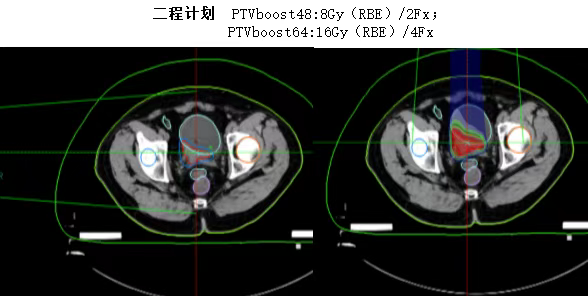

以下为碳离子治疗计划

碳离子治疗的三大核心优势

✅ 精准杀伤肿瘤,保护正常组织

●利用Bragg峰特性,高剂量精准覆盖肿瘤,同时尽量避开肠道。